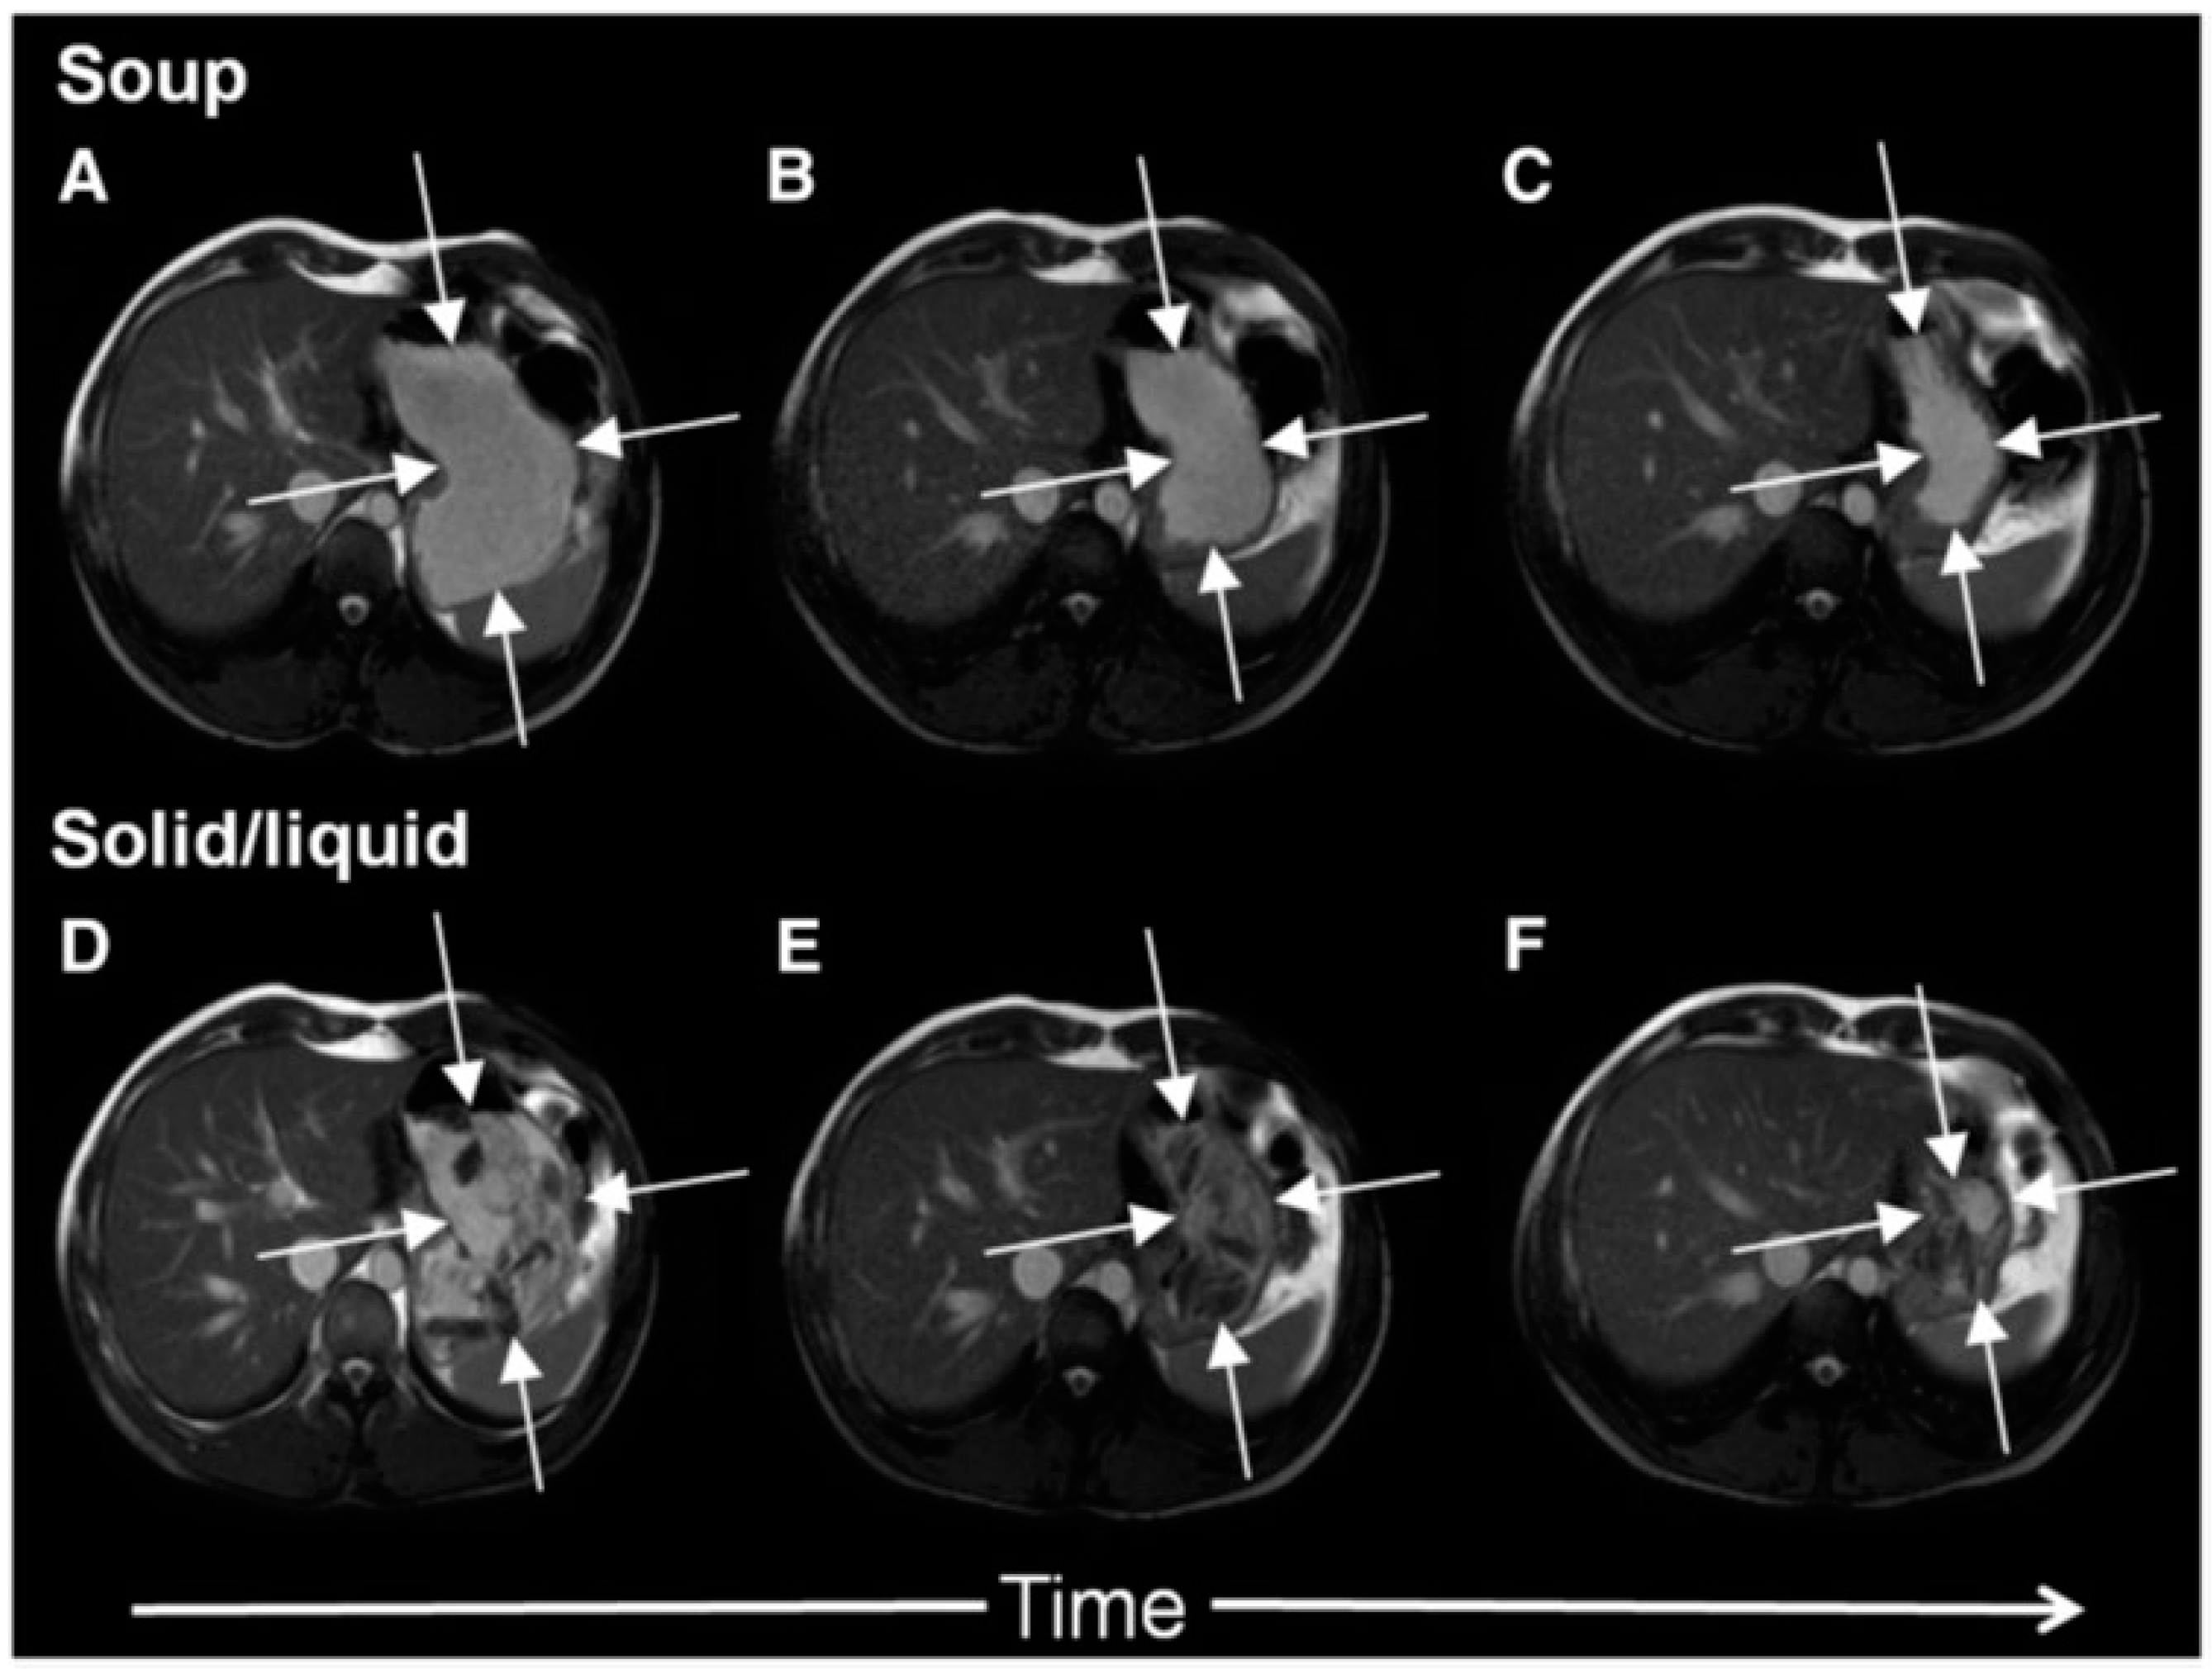

The antral contractions are typically propulsive as they commence in the mid stomach but as they approach the pylorus change to a more systolic pattern with pyloric closure occurring before all the chyme is expelled into the duodenum. This effectively restricts gastric emptying to particles <2 mm in diameter and creates shearing forces as the remaining material is forced backwards away from the contracting pylorus. The resulting forward and backward flows can be detected using flow sensitive MRI sequences as mentioned previously. The net effect is the earlier emptying of the fluid component of mixed liquid/solid meals, which make up most of what normal humans ingest. MRI images can clearly show the heterogeneity of food immediately after food ingestion, which varies according to the meal type (Figure 1). A rice pudding meal typically separates into an uppermost fluid layer above a dependent solid component, whereas a roast chicken and vegetable meal produces a very heterogeneous intragastric distribution of solid and liquid. Other more homogenous meals like porridge, soup or bread produce a uniform intra-gastric mass from which no separation of the liquid and solid phase is possible. When we compared an equicaloric rice meal with wholemeal bread, we found that while the rice pudding meal separated into a solid and liquid phase, the wholemeal bread formed a rather homogeneous mass with no clear separation of fluid and solid. While the rice meal allowed the stomach to sieve the meal and empty the fluid faster than the solid, sieving was not possible with the more homogeneous bread meal and as a consequence the gastric volume fell more slowly. In contrast, once the wheat entered the small intestine it was rapidly absorbed and the small bowel water content (SBWC) was consistently lower than after the rice meal postprandially, suggesting than any sensation of bloating after a bread meal most probably comes from gastric distension [4]. Other groups have also used MRI to document gastric sieving and its prevention by homogenization with both solid [6] and liquid [7] meals.

In Figure 2 it is shown how a typical solid meal taken with water drink (D–E) fills the stomach with heterogeneous content from which the fluid can be preferentially emptied causing a faster fall in total gastric volume and hence feeling of fullness. We compared this with the same meal blenderised to create a homogeneous soup (images A–C) and showed that the volume of the stomach fell more slowly with the soup and this was associated with more prolonged satiety [5].

Figure 2. Cross-sectional MRI images showing a stomach at 0, 60 and 120 min after ingesting either roast chicken and vegetables (panels D, E and F respectively) or the same meal blenderised to create a homogeneous soup (panels A, B and C respectively). The solid meal taken with water appears heterogeneous, fluid can be preferentially emptied reducing gastric volume and hence the feeling of fullness. The same meal when blenderised appears homogeneous, gastric volumes fall more slowly with time which is associated with more prolonged satiety. Reproduced from [5], Oxford University Press 2012, with permission.